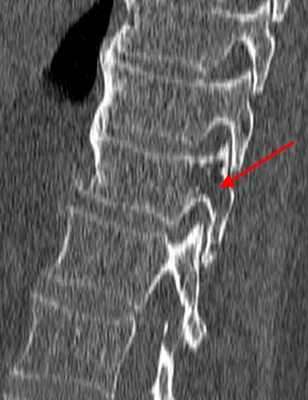

При КТ определяется участок в теле позвонка, в его дуге, ножках или суставных отростках, чаще всего имеющий форму шара или эллипсоида, или неправильную форму. Размеры гемангиомы различные - на томограммах можно можно опухоль начиная от 0,5 см. Редко встречаются гигантские сосудистые образования, занимающие практически весь объем позвонка. Рентгеновская плотность данного участка снижена по сравнению с плотностью губчатого вещества и, тем более, замыкательных пластинок.

На изображении представлен поперечный срез через позвонок. В теле позвонка - типичная гемангиома (H). Цифрой 1 отмечены утолщенные и разреженные трабекулы губчатого вещества, цифрой 2 - периваскулярные пространства, сосудистые лакуны. При компьютерной томографии они имеют низкую плотность, приближающуюся к плотности жира (гемангиолипома).

Типичная гемангиома в грудном позвонке. На аксиальном срезе - справа - отчетливо виден характерный «точечный» «рисунок», обусловленный утолщением трабекул и большим количеством периваскулярного жира.

Небольшая сосудистая опухоль в боковых отделах тела первого поясничного позвонка. При компьютерной томографии выявлен гиподенсный участок плотностью -25…-30 единиц Хаунсфилда, с типичными утолщенными и «разреженными» трабекулами губчатого вещества.

В зависимости от количества периваскулярного жира плотность гемангиомы может колебаться от +200 единиц Хаунсфилда до -40 и меньше, но практически никогда не достигает плотности жировой ткани (-100 единиц Хаунсфилда). В структуре опухоли видны множественные разреженные и утолщенные до 1-3 мм трабекулы, дающие характерный «мелкоточечный» рисунок на аксиальных срезах и «полосатый» рисунок на аксиальных и корональных изображениях. После введения контрастного вещества строма опухоли может усиливаться, зачастую весьма значительно. Наибольшую плотность сосудистые опухоли имеют в артериальную фазу контрастирования. Контраст из сосудистых лакун вымывается быстро, поэтому уже в венозную фазу плотность образования существенно снижается.

Гемангиолипома, не совсем типичная локализация в дужке грудного позвонка. Плотность отмеченного стрелкой участка приближается к плотности жира (порядка - 90 единиц Хаунсфилда).